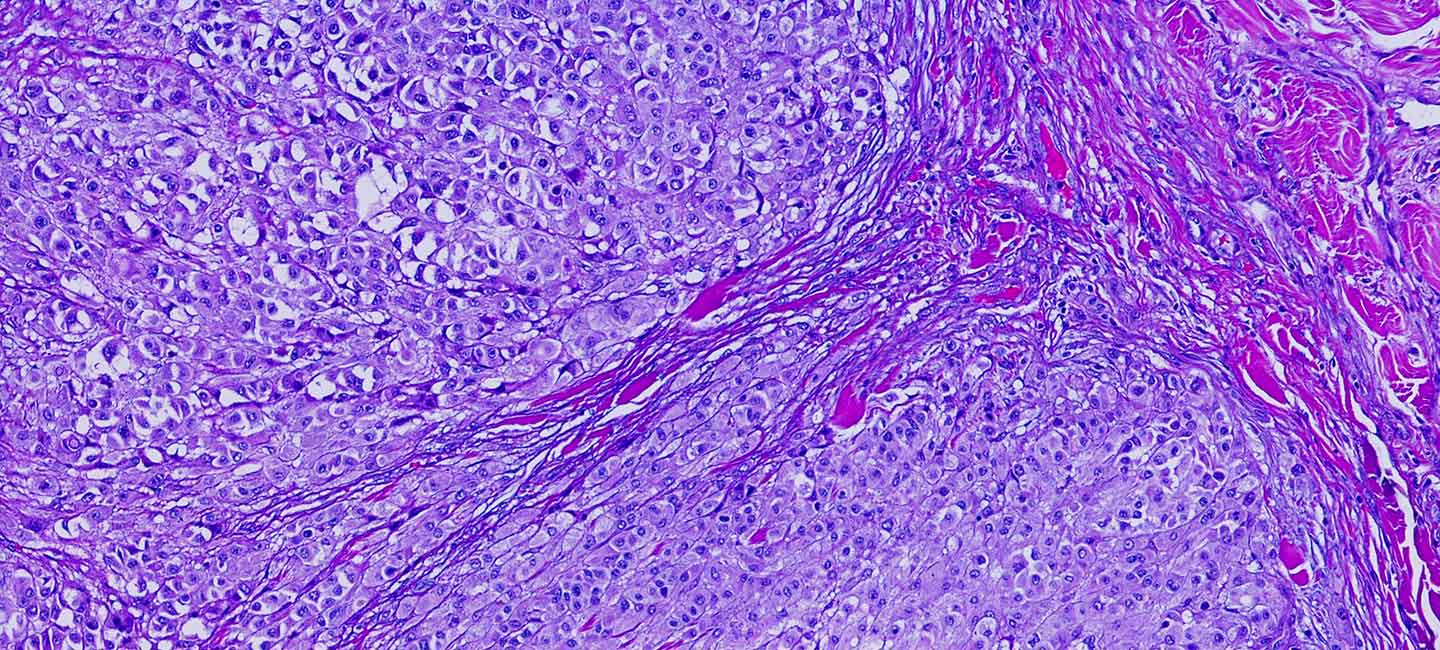

Moffitt researchers want to improve their understanding of why some metastatic melanoma patients respond better than others and determine which cellular factors contribute to these improved responses across different metastatic sites. They analyzed the RNA expression patterns of individual melanoma and immune cells from 26 patients with metastatic melanoma of the skin, brain and leptomeninges/cerebrospinal fluid, and used this information to determine the specific immune cell types that were present within each sample. They discovered that the types of cells within the tumor microenvironment varied according to the site of metastasis. Leptomeningeal melanoma metastases were characterized by an immune-suppressed environment, with a high percentage of dysfunctional CD4 and CD8 T cells that are incapable of mounting an immune response, and low levels of B cells. Alternatively, samples from brain and skin metastases were much more alike in their immune environment, with an enrichment for activated CD4 T cells.

A further analysis of dendritic cells that play an important role in therapy response showed that a subpopulation, called DC3s, were associated with improved overall survival and the presence of an active T cell immune response, regardless of the site of metastasis or treatment history. The researchers confirmed the importance of DC3s to patient outcomes through preclinical studies in mouse models.